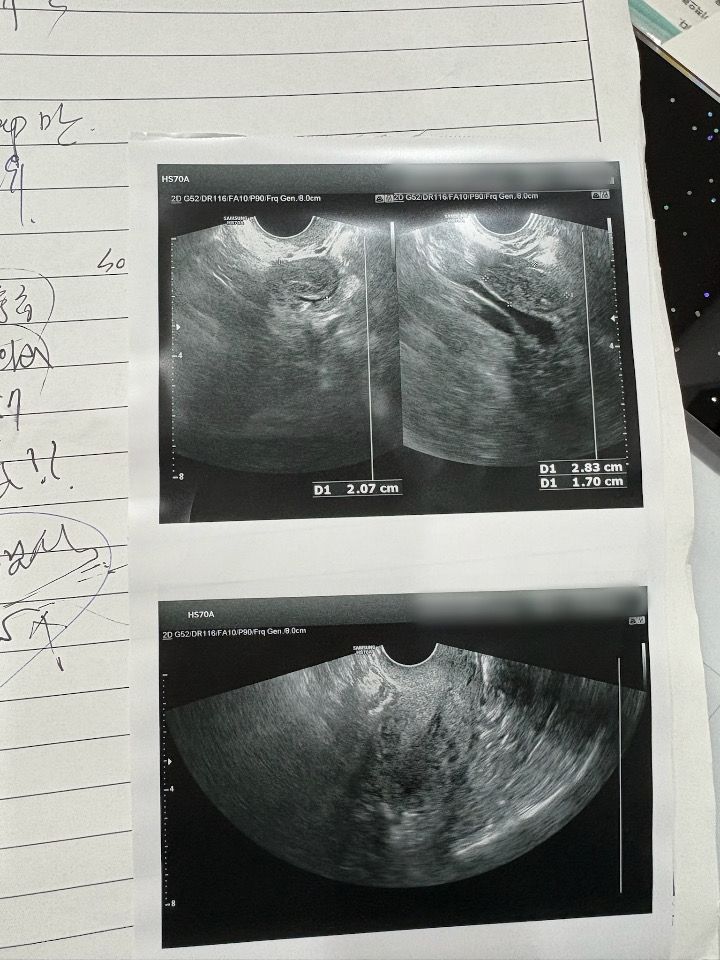

폐경되면 난소가 작아져있어야 하는데 크다고 해서 검사한 거였습니다. 초음파 사진 첨부해드립니다.

난소 안의 음영이 균질하지 않은, 저음영의 에코와 함께 고음영의 에코가 함께 관찰되는 것으로 보입니다.

전형적인 악성 종양의 양상이라고 할 순 없겠으나(피검사 수치 등을 종합하여 볼 때 ) 양성 종양이라 하더라도 크기가 점차 커지는 양상이라면 제거를 권유받을 수도 있을 것 같습니다.